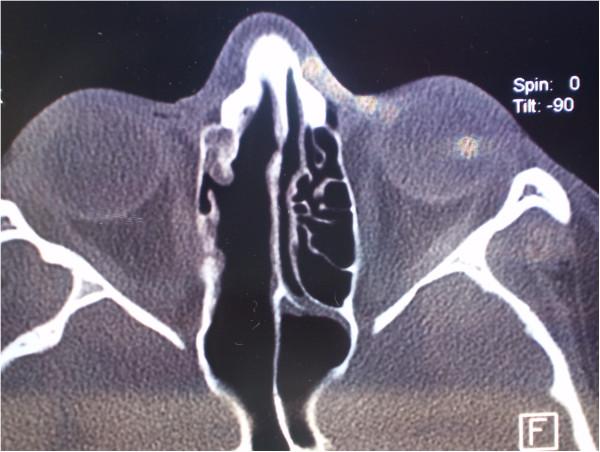

We report an unusual case of middle turbinate osteoblastoma associated with right-sided nasal obstruction and severe headache in a 14-year-old Caucasian girl. The tumor involved the right middle turbinate, complete anterior and incomplete posterior ethmoidal cells, and the frontal sinus ostium. Cribriform lamina was, in the most part, consumed by the tumor growth, while the skull base was mostly of normal bone structure.

我们报告一例不寻常的右侧中鼻甲骨母细胞瘤病例,该病例发生在一名14岁的白种女孩身上,伴有右侧鼻塞和严重头痛。肿瘤累及右侧中鼻甲、完整的前筛窦和不完整的后筛窦以及额窦开口。筛状板大部分被肿瘤生长所破坏,而颅底大部分骨质结构正常。